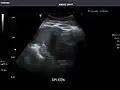

Spleen -

Spleen: Normal in size.